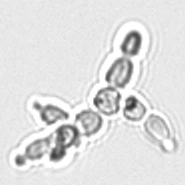

Модуль производит подсчёт частиц, используя для этого метод проточной плоскостной (ламинарной) цитометрии с цифровой визуализацией и идентификацией c помощью нейросети (DeepCNN).

Точная автоматическая классификация форменных элементов мочи с уровнем соответствия микроскопии >95%.